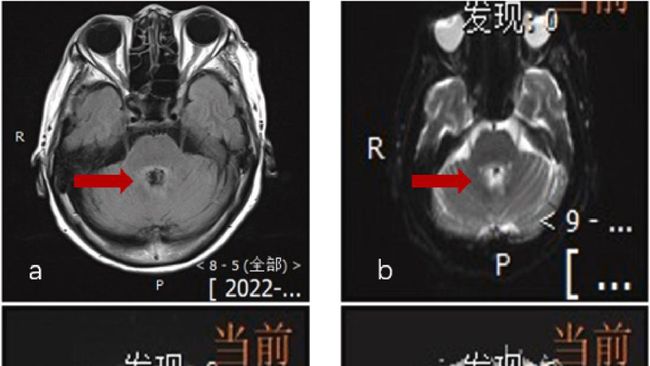

Foto: Heliyon case report

Mulanya, dokter mengira dia mengidap tumor otak. Sebab, dari hasil CT scan terlihat ada lesi di bagian otaknya.

Akan tetapi, saat pemeriksaan lebih lanjut dengan jarum yang dimasukkan ke tulang belakang untuk menguji cairan, terungkap penyebab sebenarnya. Wanita tersebut terinfeksi Balamuthia mandrillaris, yaitu amoeba atau organisme bersel tunggal yang menyebar ke otak dan bisa menyebabkan kematian.